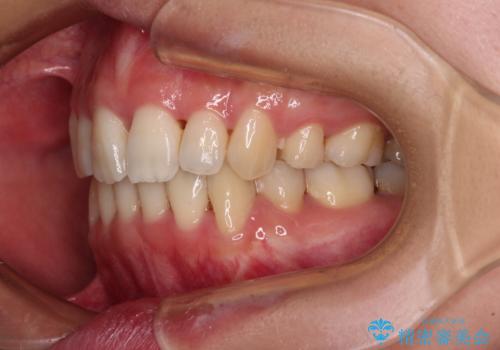

Eラインを改善したい ハーフリンガルによる抜歯矯正

- 口元の突出感を気にして来院された患者様です。

上下左右の第一小臼歯4本を抜歯して口元を下げる治療計画としました。

舌の突出癖が強く、口元を引っ込める力に拮抗してしまい、抜歯スペースを閉じるまでに時間がかかりました。

また途中出産もありましたが、無事に治療を終えることができました。